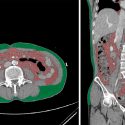

Colombia: logran y patentan dispositivo que segmenta y cuantifica los tejidos corporales

Un dispositivo que segmenta y cuantifica de manera automática los tejidos corporales, denominado CAVAT (Computed Assisted Visceral Adipose Tissue), creado en la Universidad de los…